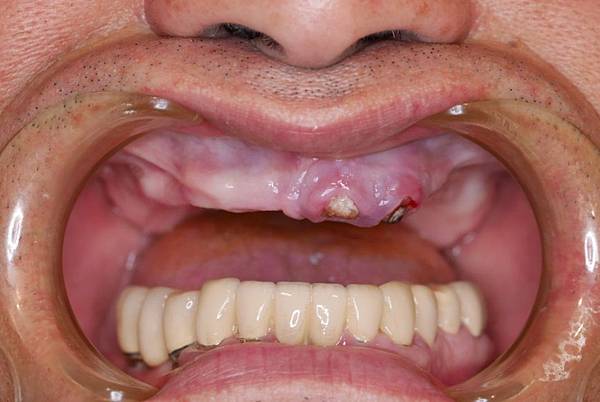

個案故事65

歲的陳媽媽活動假牙戴了好幾副 ,牙齒卻反而是越戴越少 ,如今戴的這副活動假牙吃飯時還會在嘴巴裡跑來跑去,不僅使用不便,也容易卡菜渣,讓她愈來愈討厭吃飯,人也日漸消瘦,為了陳媽媽的身體健康,她的兒子便趕緊帶她來做A11 on 4固定假牙(植牙)。